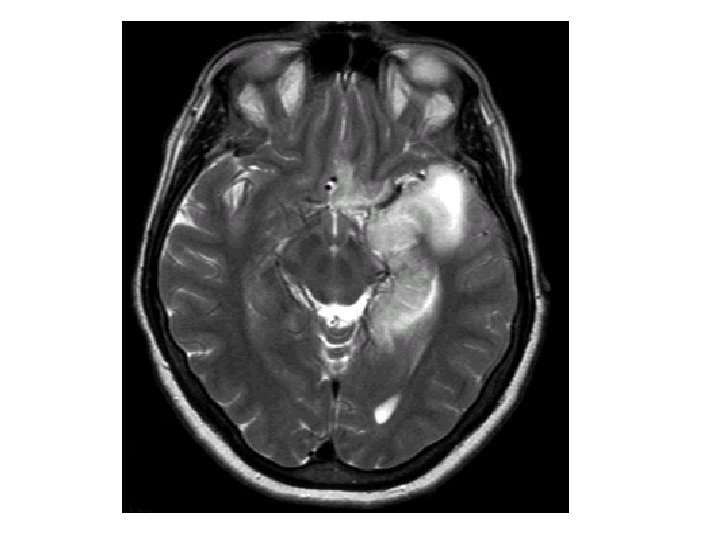

Expression clinique • L’affection est strictement liée au SNC • présence de lésions herpétiques orales ou faciales rarement constatée (moins de 10%) n’a pas de valeur particulière. . • Aucun signe pathognomonique, examens complémentaires nécessaires.

Ponction Lombaire • L’analyse du LCR montre: – Liquide lymphocytaire (10 à 500 éléments) – Protéinorachie modérément élevée (0. 5 à 1. 5 g/l) – Glycorachie normale. – (Présence d’interféron a) – Absence de germe au direct